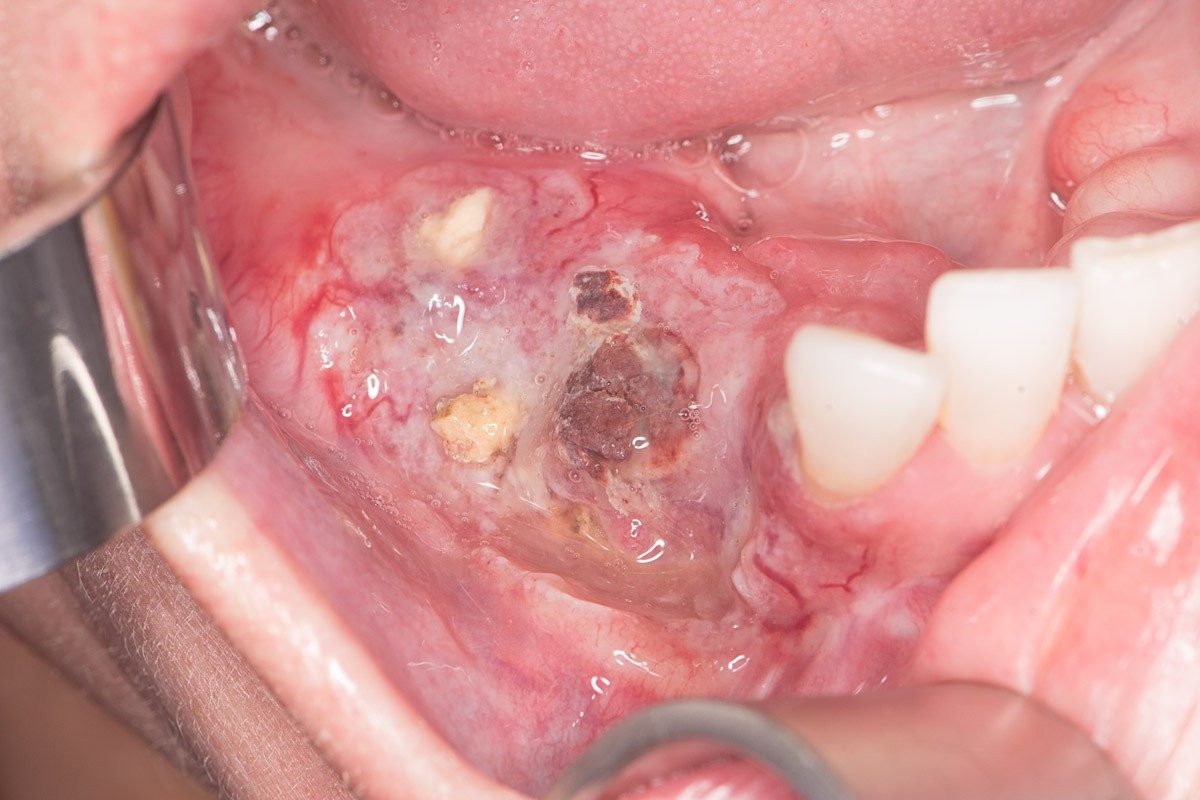

Oral cancer refers to malignant tumors that develop in the oral cavity, including lips, tongue, floor of the mouth, buccal mucosa (inner cheeks), gums, hard palate, and retromolar trigone. It is a subset of head and neck cancers and is also known as oral cavity cancer. The majority of oral cancers are squamous cell carcinomas, meaning they develop from the thin, flat cells lining the mouth.

Signs of oral cancer may vary depending on location and severity. Early signs are often subtle and painless, making regular dental checkups crucial.

- Persistent mouth sores that do not heal within 2 weeks

- Red or white patches (erythroplakia or leukoplakia)

- Unexplained lumps or thickening in the oral tissues

- Visible lesions or growths